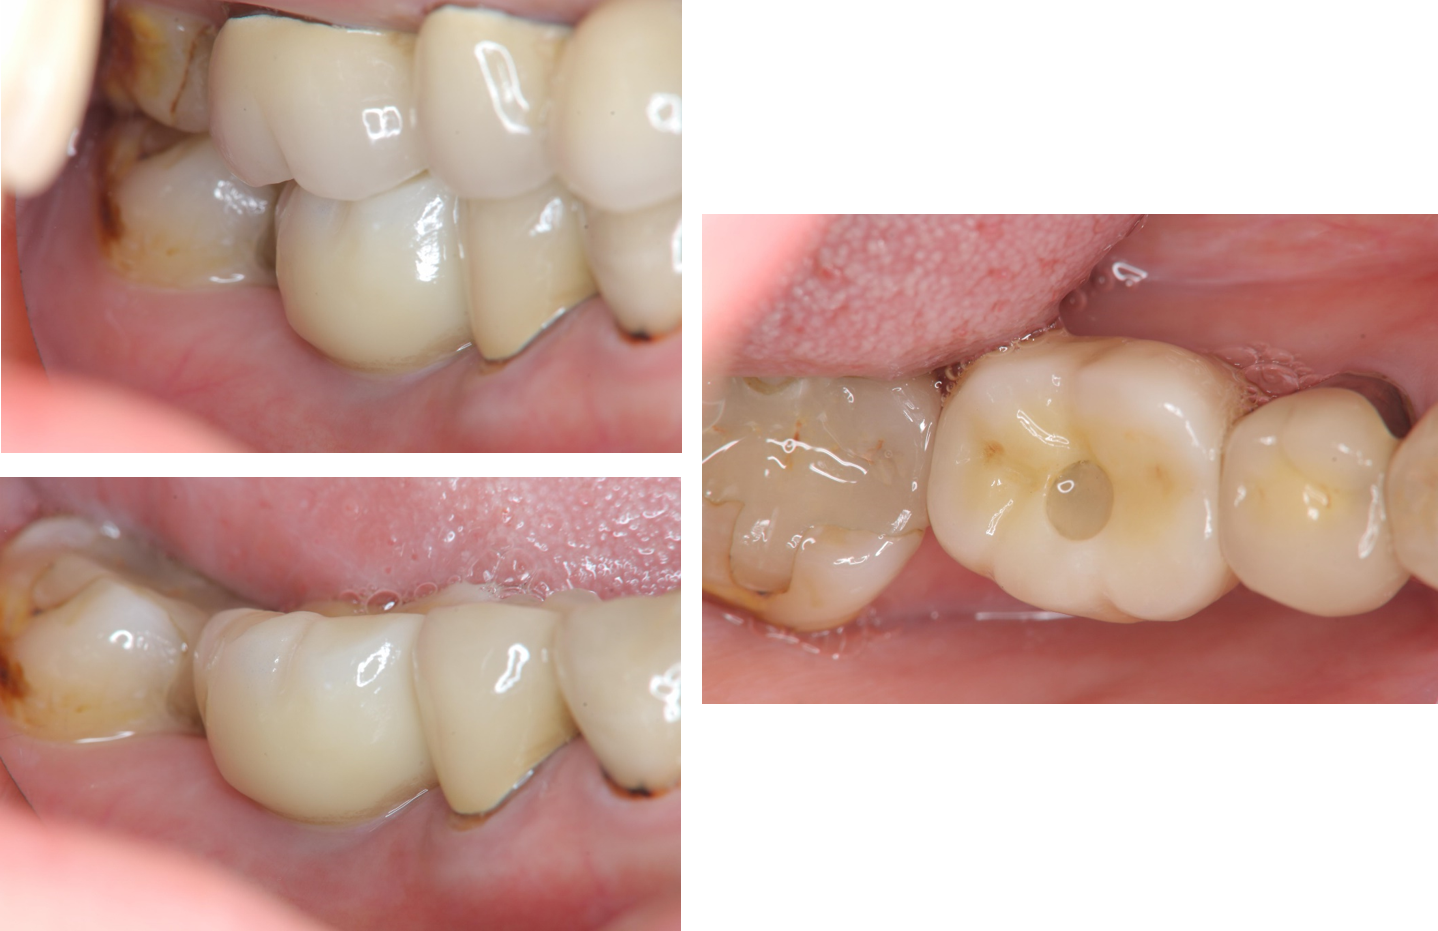

治療後,口內適應良好

治療後,植體周圍健康